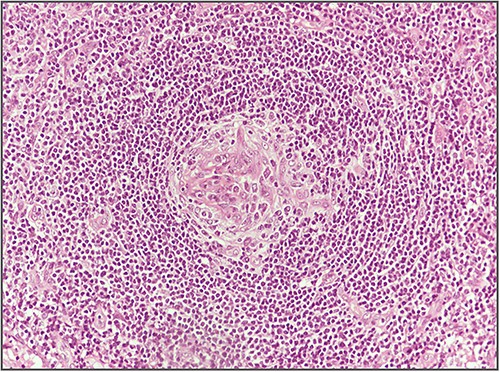

Blood investigations including hematological and biochemical tests revealed a low lymphocytes count with a consequent increased neutrophils percentage, and an increased protein C reactive (PCR) value. Oncological markers were normal. He was also tested for HIV infection, HHV-8, and Epstein–Barr virus with negative results. Positron emission tomography (PET) was performed with evidence of increased metabolic activity at the site of the mass. A suspicious diagnosis of Schwannoma or liposarcoma was made. The patient underwent CT-guided percutaneous biopsy with extemporary histological diagnosis of hyaline-vascular variant Castleman disease. The patient was subdue to laparoscopic removal of the mass. The mass was located near the duodenum without other structures involvement, from which it was isolated and entirely resected comprehending the intact capsule. No intra- and post-operative complications were recorded. The microscopic examination revealed the presence of a single lymph node measuring 7 × 5 × 4.5 cm with clear margins and an architecture characterized by the presence of small follicles distributed over the entire surface, lacking clear centers and polarization (primary follicle or atrophic follicle type), some with prominent vascularization and fibrosis (hyaline-vascular transformation), hyperplasia of the CD21+ follicular dendritic cells (Figs 3 and 4), and a “target” arrangement of the mantle lymphocytes. Large follicles with hyperplastic germinative centers and follicles with small centers duplicate germinatives, marked paracortical interfollicular vascular hyperplasia, and poor polytypic interfollicular plasmacytosis with very low proportion of IgG4+ plasma cells, coexist (Fig. 5).

Hyperplasia of follicular dendritic cells (staining of follicular dendritic cells with anti-CD21 antibody).